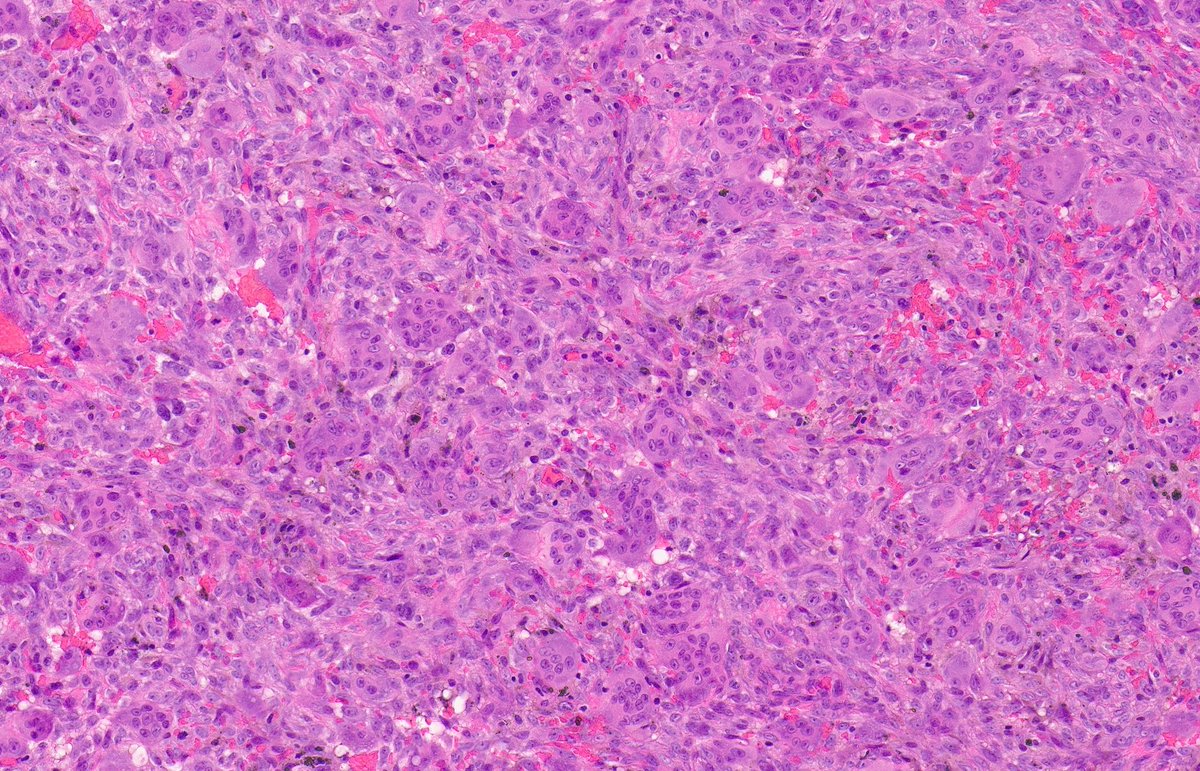

MALIGNANT PERIPHERAL NERVE SHEATH TUMOUR. Underlying NF1. IHC: SOX10, H3k27me3. NB: spindle-epithelioid cells with pale amphophilic cytoplasm; ovoid-round nuclei with moderate pleomorphism and conspicuous mitotic activity; variable collagenous-myxoid stroma.

1

21

60